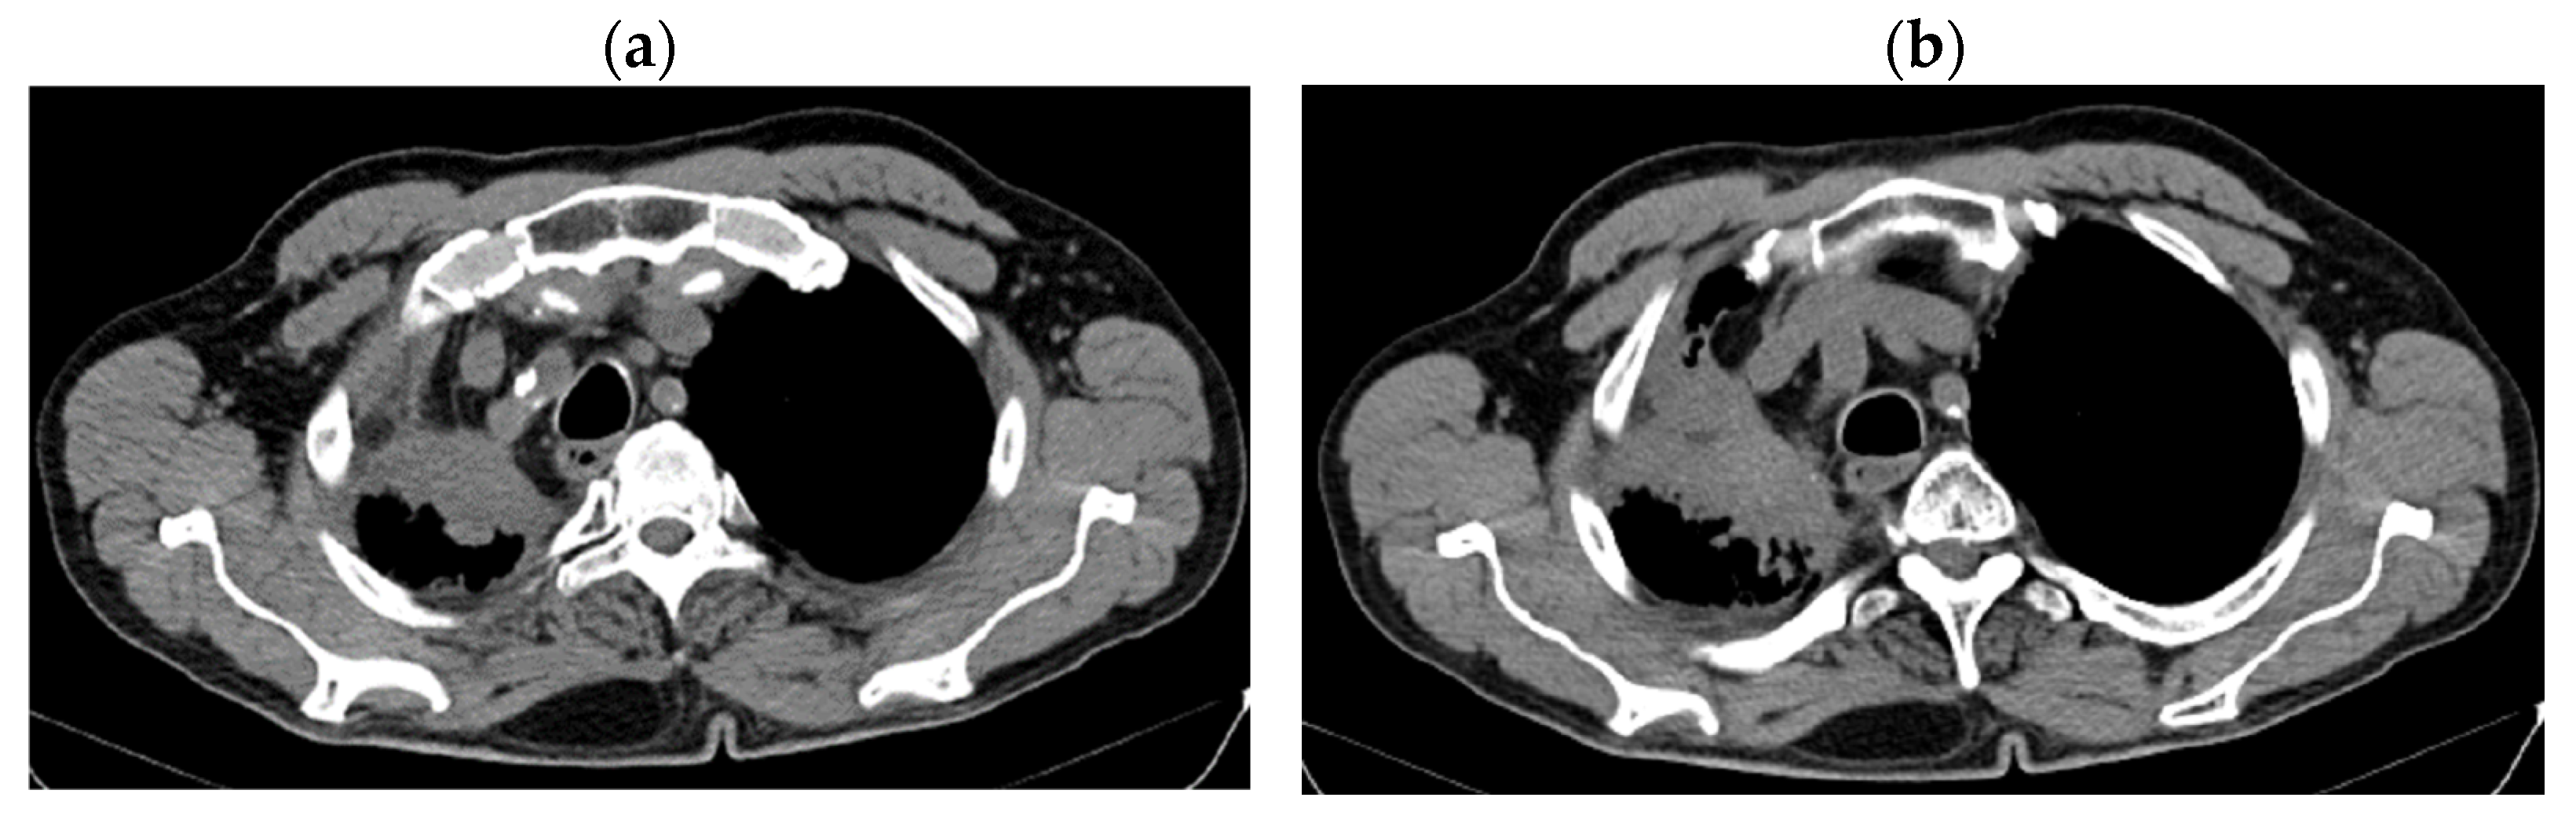

2. Case Presentation

2.1. Systemic Third-Line Therapy (4xDocetaxel) Was Initiated 04–07/2020

2.2. Monitoring 2022: Oncological Commission 1910/16.08.2022

2.3. Oncological Committee 07/25/2023 Recommended